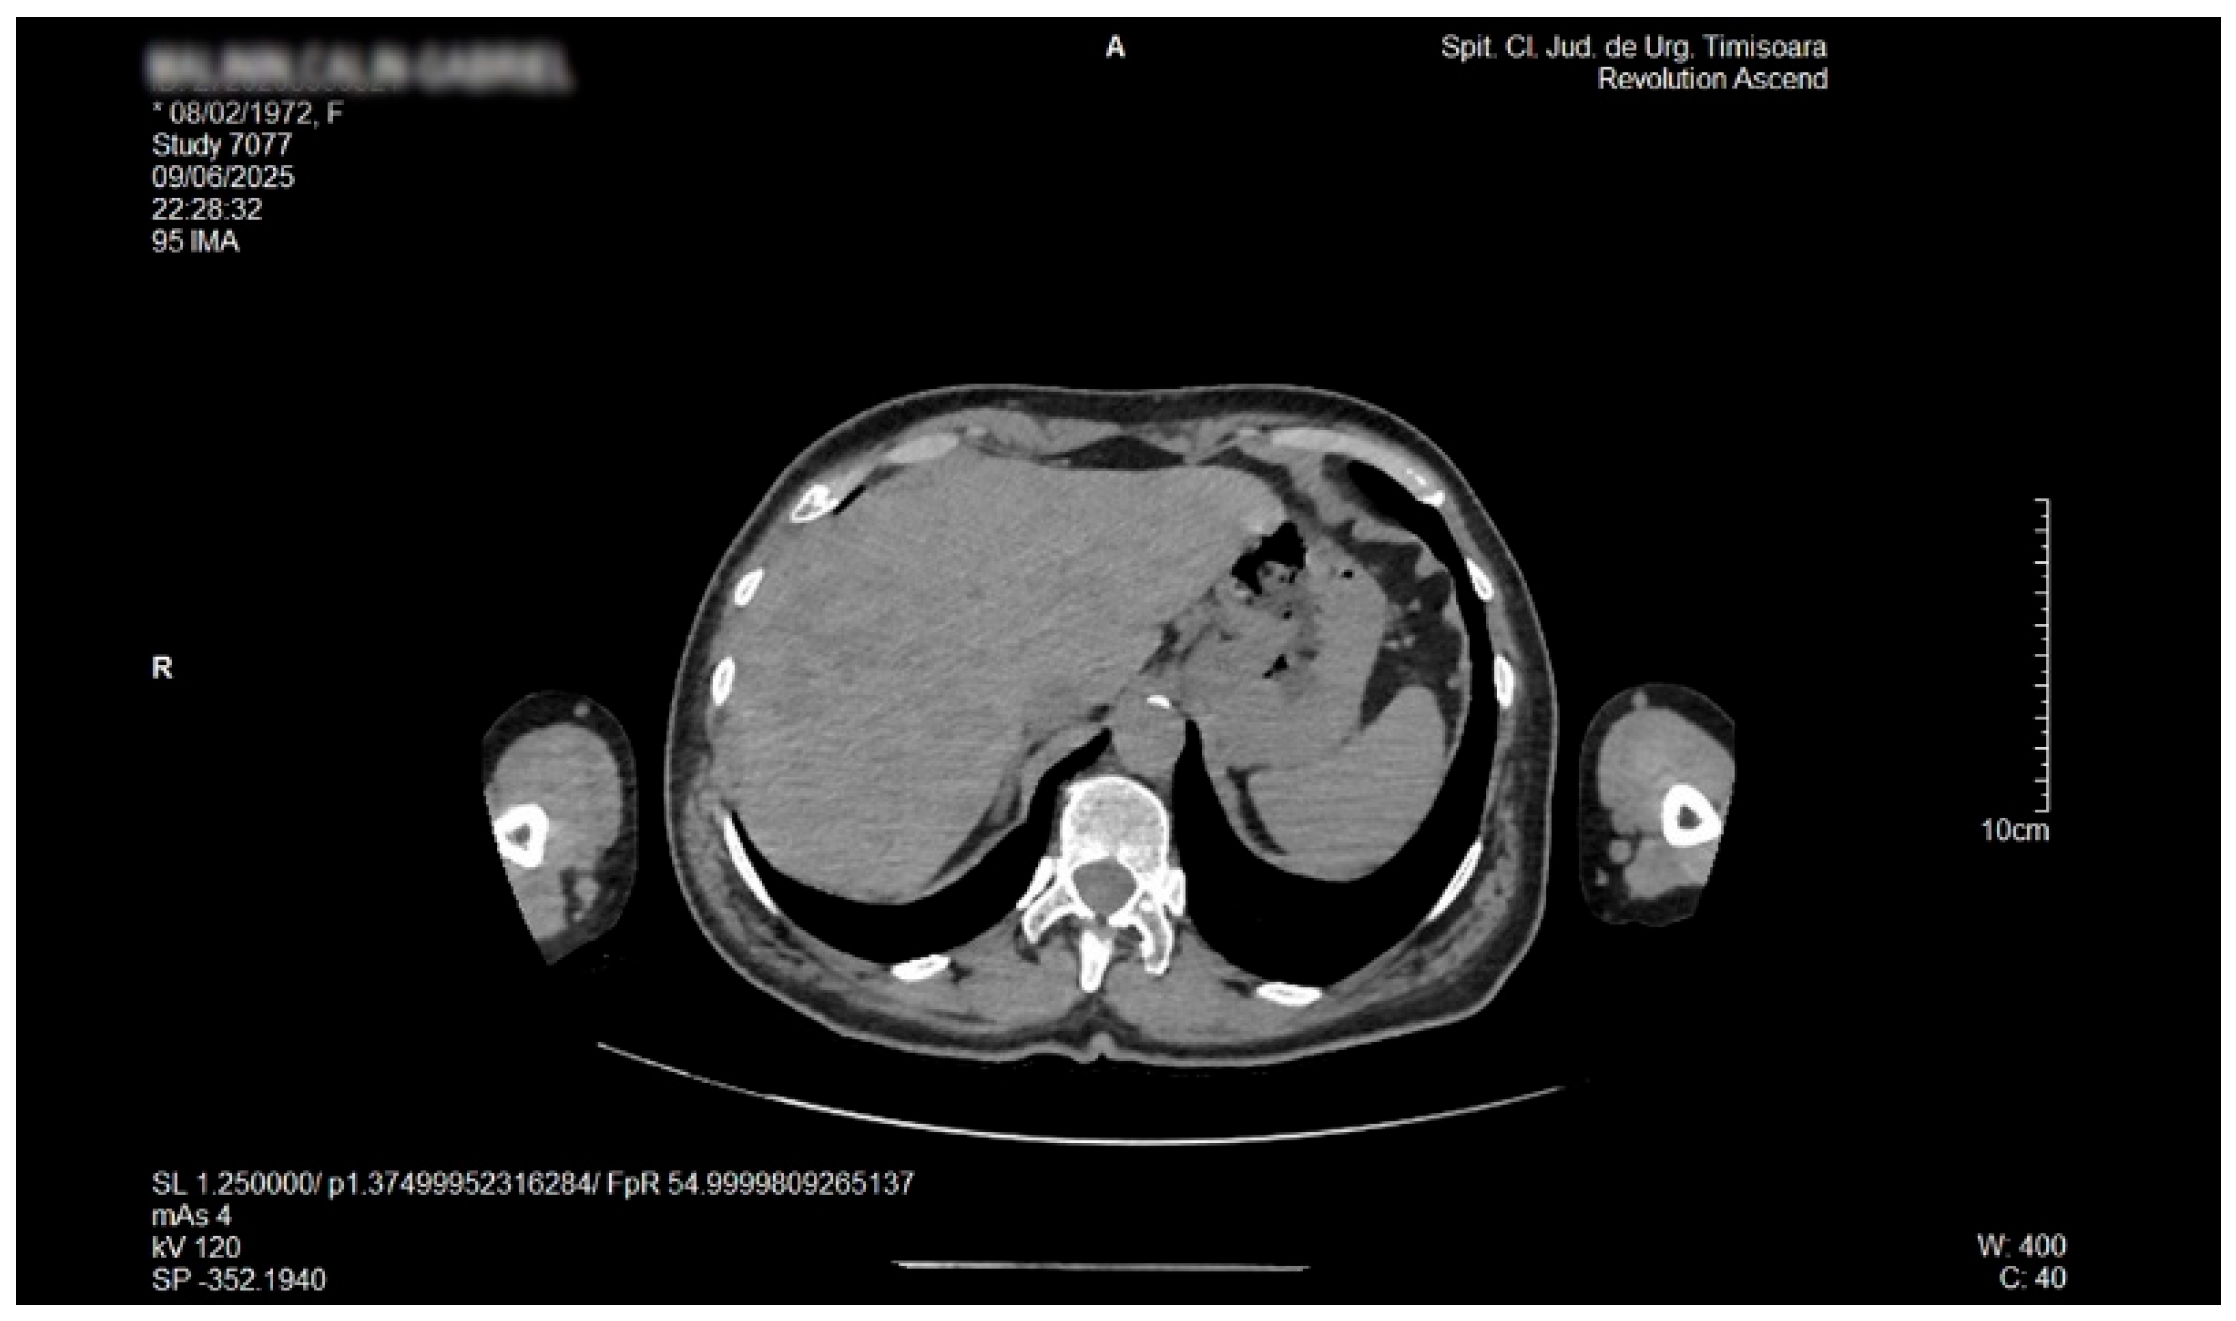

Detailed Case Description